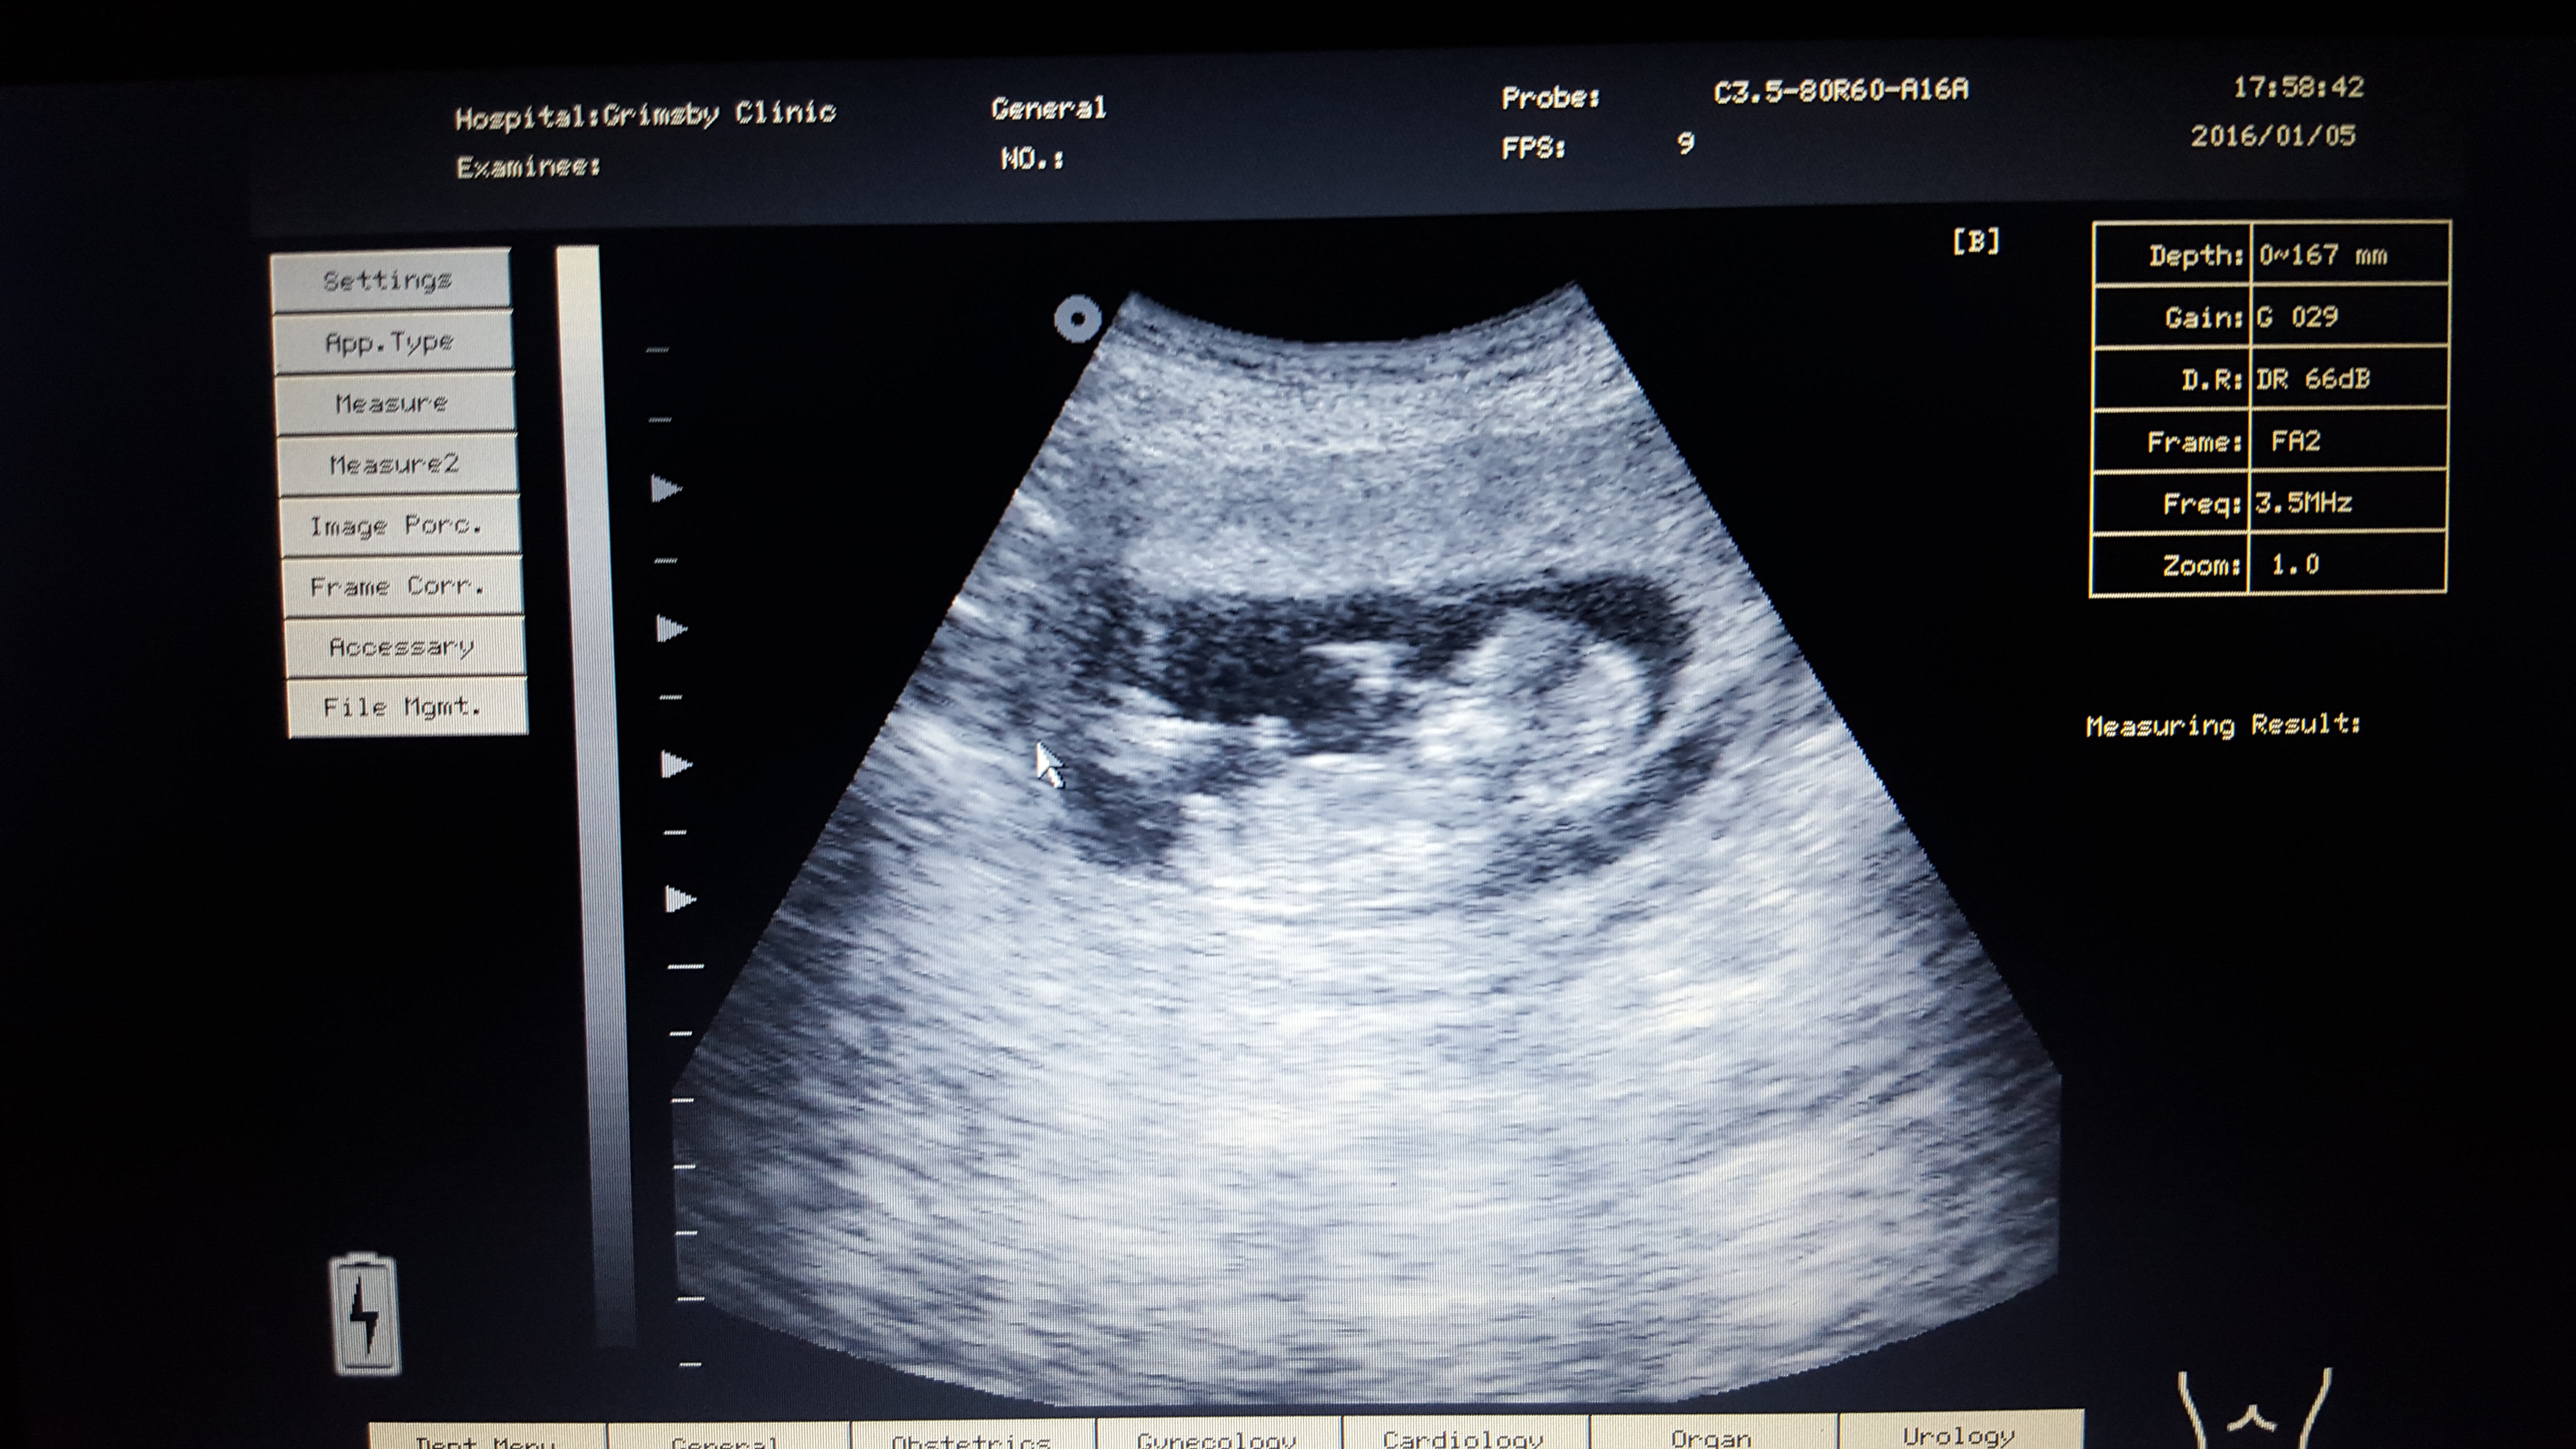

Pink or blue? These are taken at 13+3

Babies hands were around genital area alot so may of caught that in some of the photos!